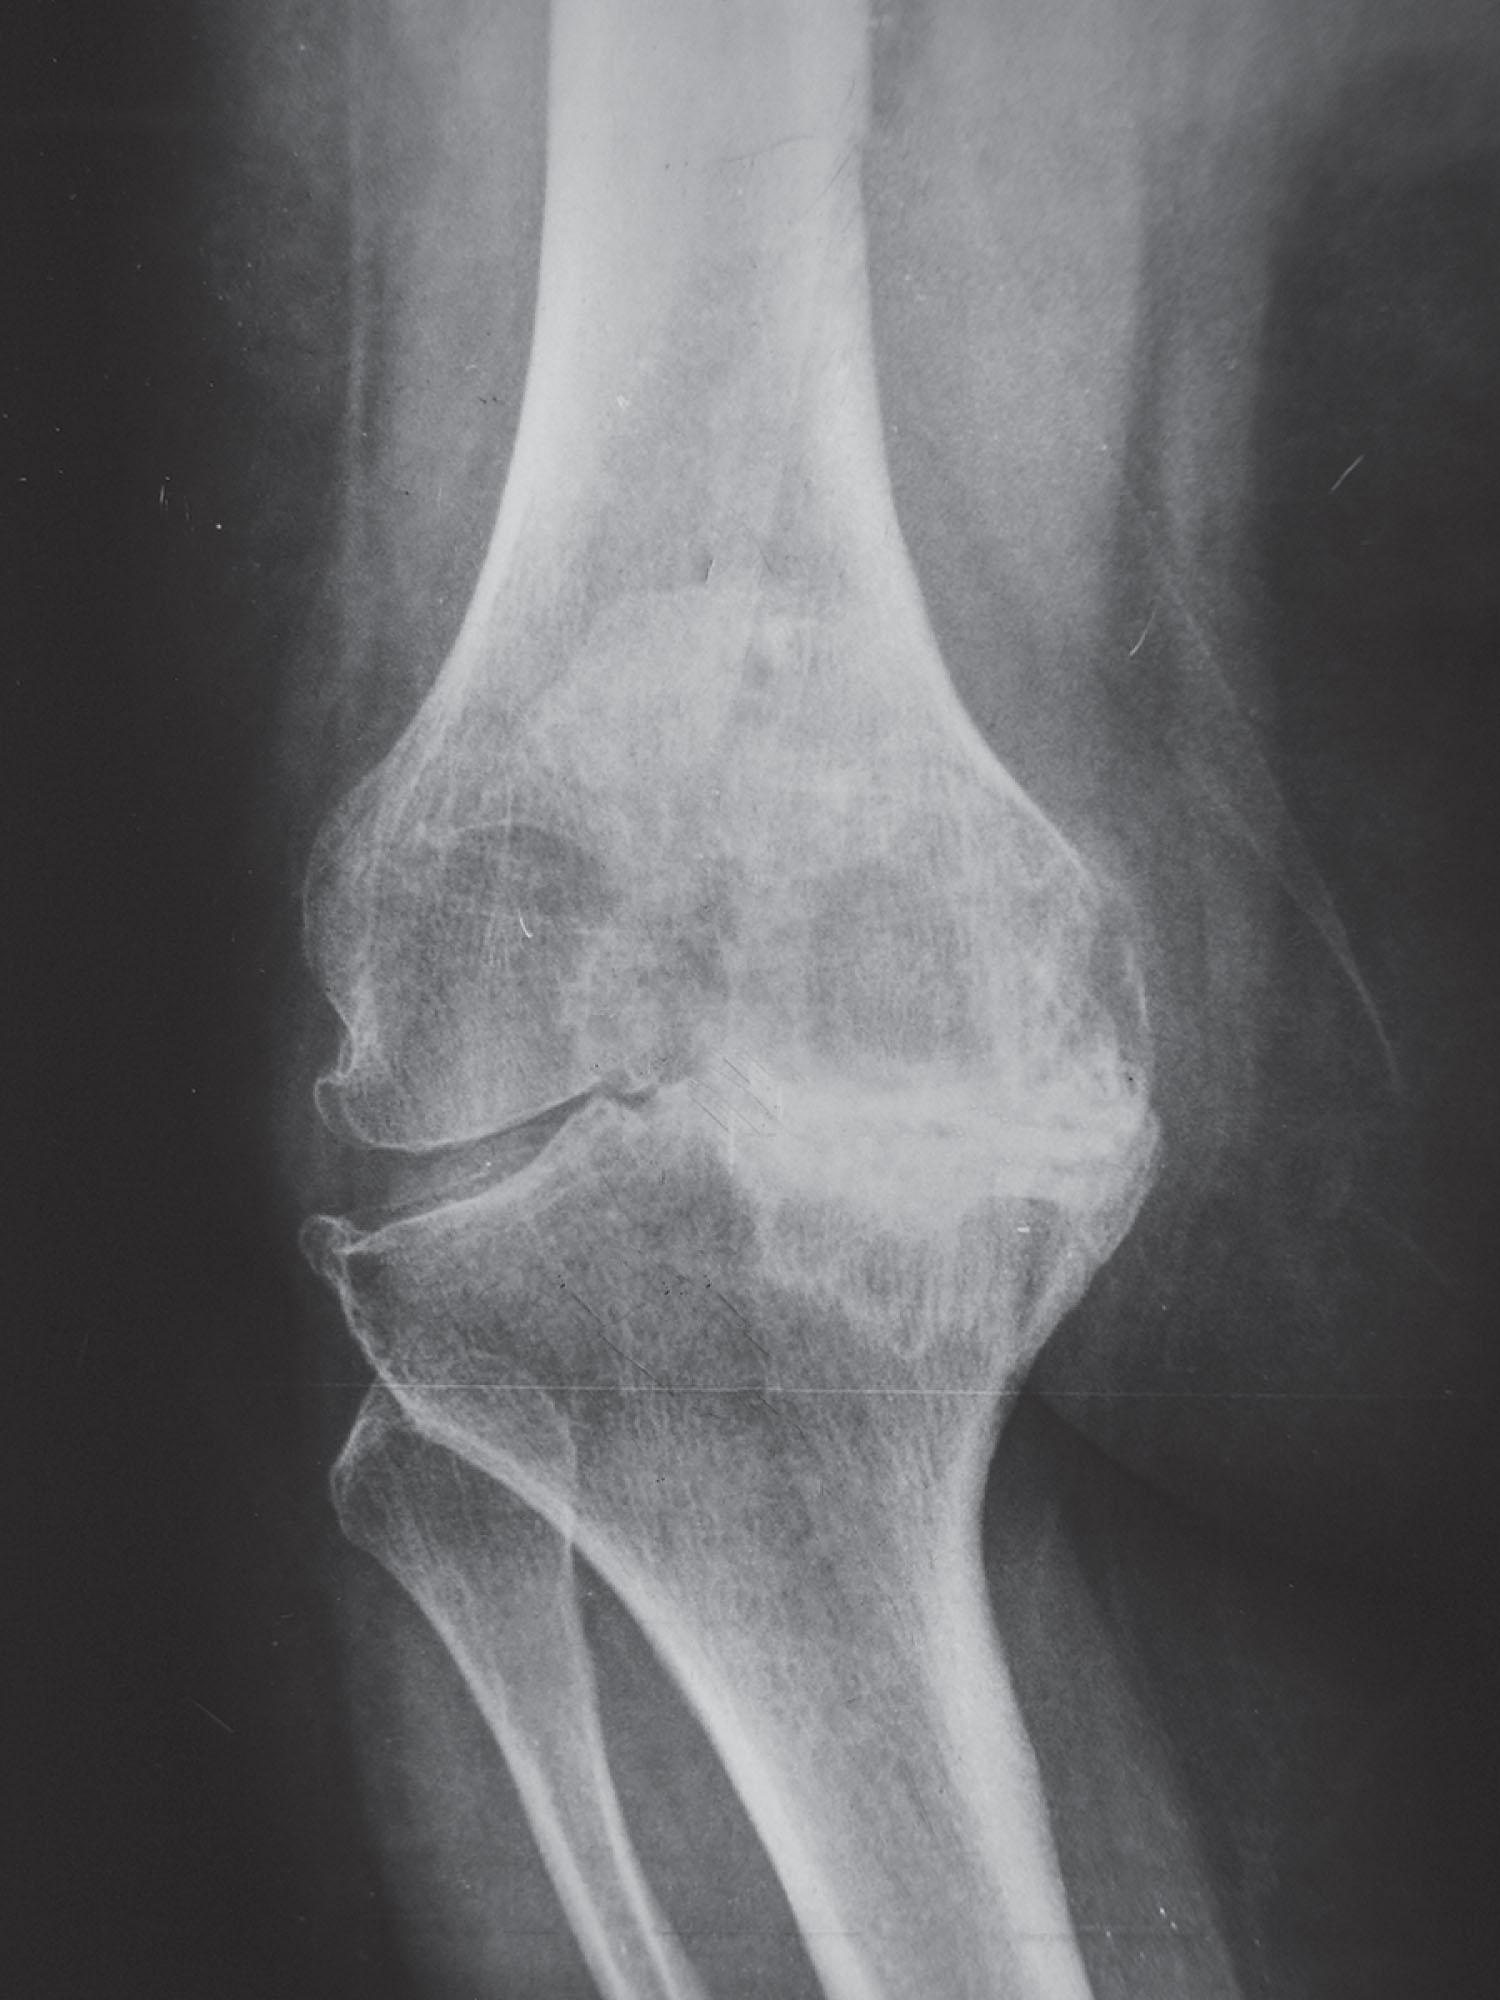

Type E 0: Articular deformity

The entire arthritic process, bone loss and deformity, is confined to the articular surfaces of femur and tibia with no extraarticular deformity beyond ( Fig. 9.21 ). The TEA (i.e., the approximate attachment of the ligament origins) is normal as is its orientation with the femoral shaft and mechanical axes.

Fig. 9.21, A classical presentation of a type E 0 deformity that is confined to the articular surfaces.